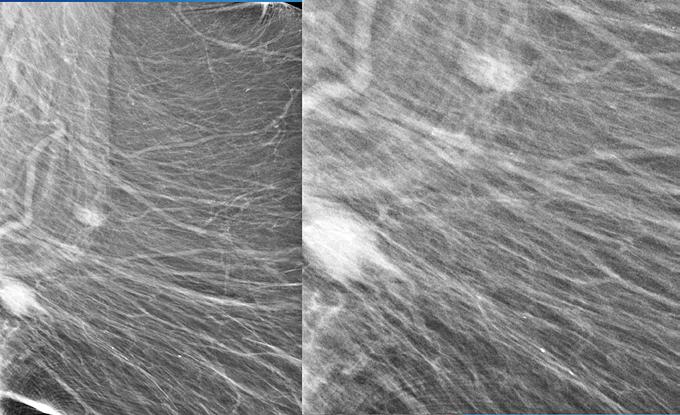

Patternuri de infiltrare a măduvei osoase în MM decelate prin IRM (figura )

Leziunile infiltrative și nodulare întâlnite în MM prezintă hiposemnal T1 datorită absenței grăsimii și cantității crescute de plasmocite din interior; ele prezintă în general un semnal T1 scăzut în comparație cu discurile intervertebrale și musculatura. Pe de altă parte, leziunile prezintă aspect hiperintens pe secvențele T2 FAT SATURATION sau STIR datorită conținutului ridicat de apă și celule, aspect similar altor leziuni osoase maligne[19].

Leziunile MM sunt prezente predominant în scheletul axial și anume vertebre (66%), pelvisul osos (30%) și într-o măsură mai mică la nivelul scheletului extra-axial (coaste, schelet apendicular) [20] În literatură sunt descrise cinci tipuri de infiltrare a măduvei osoase în mielomul multiplu: măduvă cu aspect normal, infiltrare focală a măduvei osoase, infiltrare difuză, infiltrare de tip “sare și piper” și infiltrare combinată focală și difuză [21, 22]; Există o multitudine de studii apărute în literatură care corelează aceste tipuri de infiltrare medulară cu modificările vizualizate la examenele morfo-patologice [23, 24]. În majoritatea cazurilor de MM (28%) se observă un aspect normal al măduvei osoase, cu hipersemnal T1 omogen al acesteia; în cazul infiltrarii, focale se observă diverse leziuni focale T1 hipointense, care pot apărea oriunde la nivelul scheletului; în cazul infiltrării difuze, se observă hiposemnal T1 difuz la nivelul intregii măduve osoase, uneori în caz de infiltrare severă, semnalul fiind chiar mai redus decât cel al discului intervertebral. În doar 3% din cazuri se observă un model de tip „sare și piper” și în 11% din cazuri se poate observa un model mixt de infiltrare nodulară și difuză [22, 25]

Tipuri de afectare medulară în mielomul multiplu: aspect normal imagistic(a), infiltrare focală(b), infiltrare difuză(c) infiltrare de tip ‘sare și piper’, infiltrare mixtă de tip focal și difuz(d). Departamentul de Radiologie al Spitalului Clinic Municipal de Urgență - Timișoara/RO